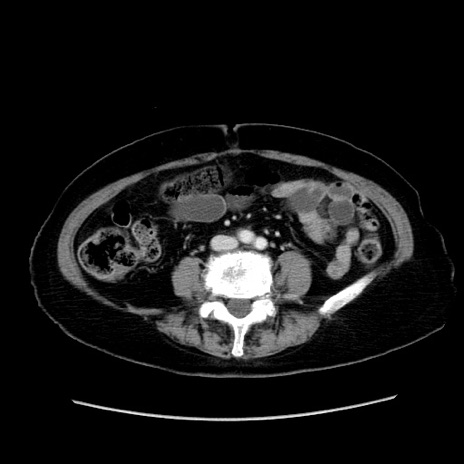

症例19(横断像)

【症例】80歳代女性

【主訴】下腹部痛

【現病歴】約8時間前より下腹部痛の出現あり、救急外来受診。

【既往歴】両側付属器切除

【身体所見】意識清明、下腹部正中に手術痕あり、その部位に一致して圧痛と反跳痛あり。腸蠕動音は亢進。

【データ】WBC 9300、CRP 0.15